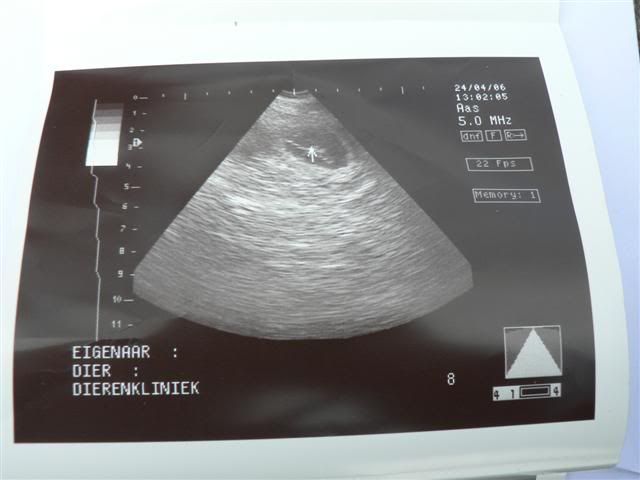

Vandaag, op de sterfdag van Bolletje zagen we op de echo dat Pientje puppies krijgt. Er waren er 5 heel goed te zien. Over het aantal kon ze moeilijk iets zeggen omdat ze verlegen waren en zich achter elkaar verscholen. Het zal geen supergroot nest worden maar de dierenarts verbaast zich nergens meer over......

Pien is op 27 mei uitgerekend, dat is dan 63 dagen na de 2e dekking.